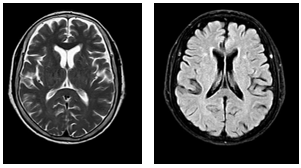

-         Chụp MRI sọ não có tiêm thuốc cản quang: Hình ảnh thoái hóa myelin quanh não thất bên và trung tâm bán bầu dục hai bên. Dày nhẹ niêm mạc xoang sàng hai bên. Hiện không thấy nốt ngấm thuốc bất thường nhu mô não.

Hình 4: MRI sọ não sau tiêm thuốc cho thấy các ổ thoái hóa myelin rải rác vùng chất trắng, không ghi nhận tổn thương ngấm thuốc bất thường nhu mô não.

Nhận xét: Sau 3 tháng điều trị đích bằng Osimertinib (80mg/ngày), bệnh nhân ghi nhận đáp ứng điều trị rõ rệt. Lâm sàng cải thiện tốt. Trên cắt lớp vi tính lồng ngực, khối u phổi trái giảm kích thước, hạch trung thất thoái triển, tràn dịch màng phổi giảm đáng kể. Theo tiêu chuẩn RECIST 1.1, bệnh nhân được đánh giá đáp ứng 1 phần. Sau 6 tháng điều trị đích, bệnh nhân cải thiện rõ về mặt lâm sàng, toàn trạng ổn, xét nghiệm chất chỉ điểm khối u giảm rõ rệt, cắt lớp vi tính bụng, não không ghi nhận tổn thương thứ phát. Kết quả cho thấy hiệu quả kiểm soát bệnh kéo dài của Osimertinib.

Liệu pháp điều trị đích ngày càng đóng vai trò quan trọng trong điều trị ung thư biểu mô tuyến của phổi, EGFR (+). Việc phát hiện đột biến sớm có ý nghĩa quyết định trong lựa chọn hướng điều trị. Bệnh nhân trong ca lâm sàng này được lựa chọn điều trị Osimertinib 80mg/ngày ngay từ đầu đã mang lại đáp ứng điều trị sớm và rõ rệt. Sau 3 tháng điều trị, bệnh nhân đáp ứng một phần theo tiêu chuẩn RECIST 1.1 với sự thu nhỏ khối u nguyên phát, thoái triển hạch trung thất, tràn dịch màng phổi giảm đáng kể. Sau 6 tháng điều trị, bệnh nhân tiếp tục duy trì đáp ứng lâm sàng ổn định, không còn ghi nhận tổn thương ngấm thuốc bất thường,tổn thương xương ổn định, cho thấy hiệu quả kiểm soát tổn thương hệ thần kinh trung ương và di căn xương của Osimertinib. Trong quá trình điều trị, bệnh nhân ghi nhận sụt cân mức độ nhẹ, không ghi nhận các tác dụng phụ thường gặp như tiêu chảy, ban da mức độ nặng, không cần giảm liều hay gián đoạn điều trị. Kết quả của ca lâm sàng này phù hợp với kết quả nghiên cứu FLAURA, cho thấy Osimertinib cải thiện đáng kể thời gian sống thêm không tiến triển và khả năng kiểm soát tổn thương hệ thần kinh trung ương so với EGFR-TKI thế hệ trước [4]. Thông qua ca bệnh này, nhấn mạnh vai trò của xét nghiệm sinh học phân tử  trong cá thể hóa điều trị và khẳng định hiệu quả, tính an toàn của Osimertinib trong thực hành lâm sàng.